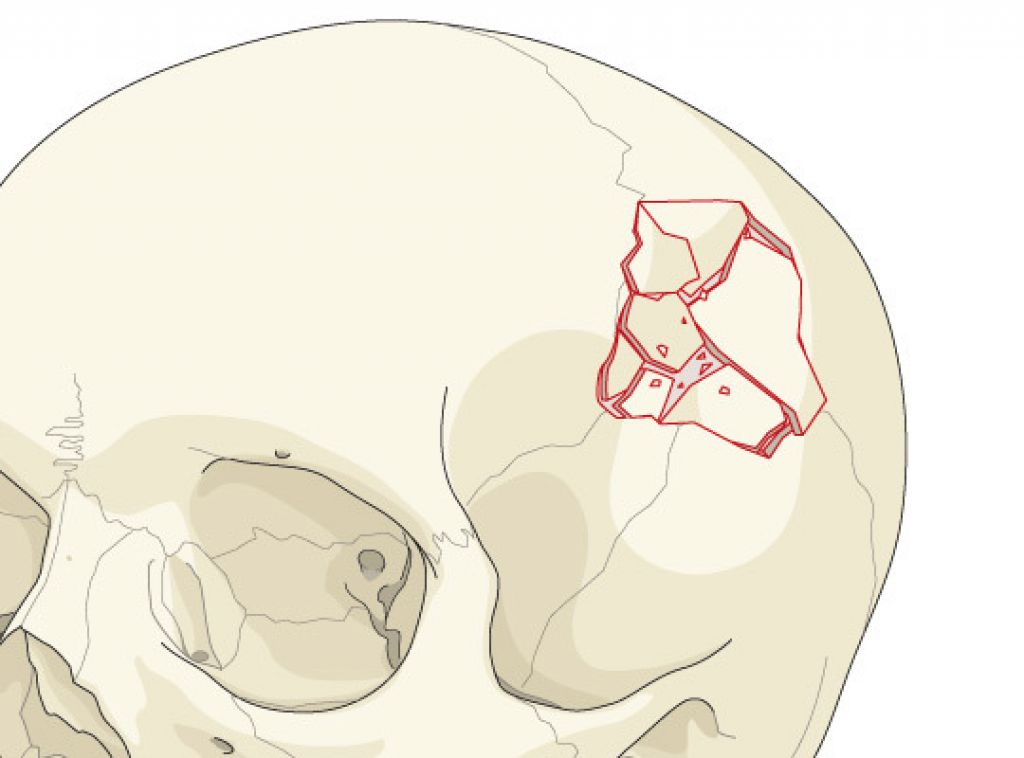

Закрытый перелом головы